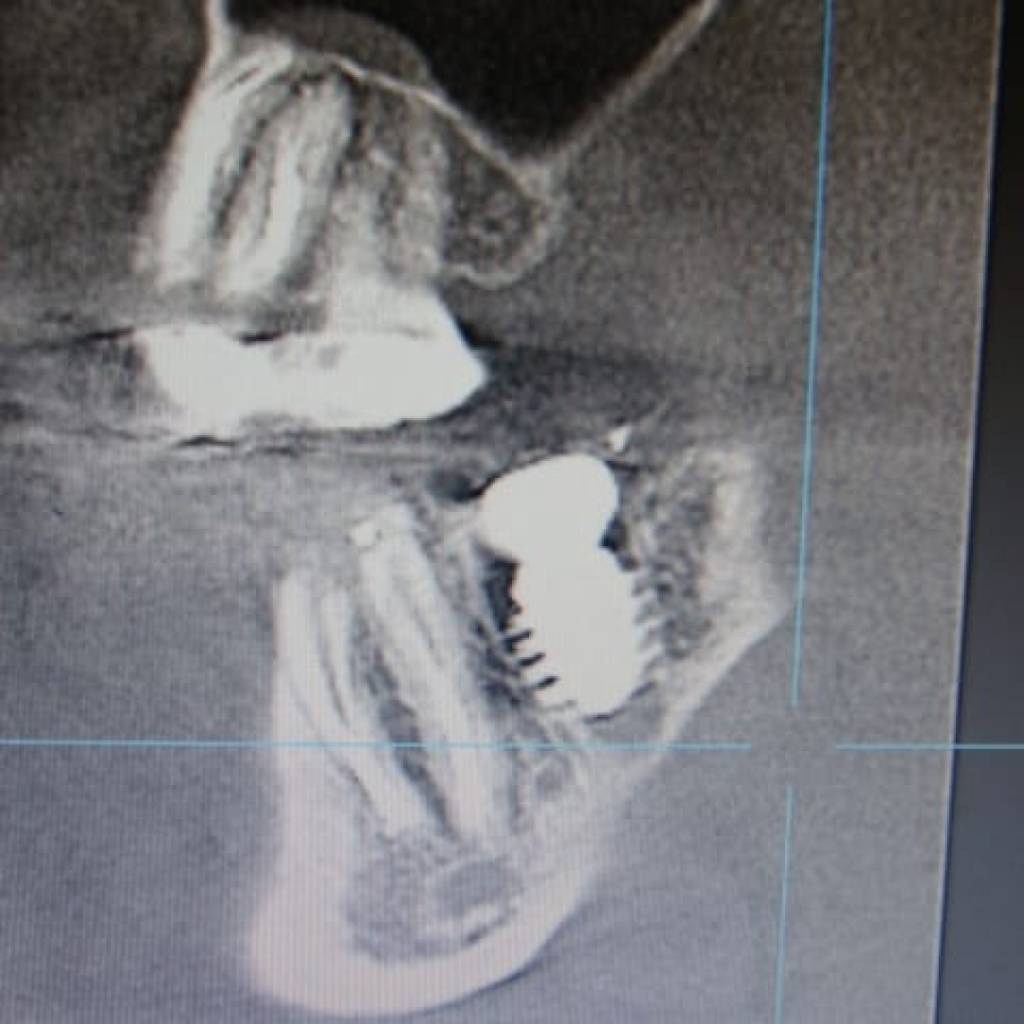

- Установка имплантата AnyRidge (Ø 8,0 мм, h 10,0), с торком 50-55 (данные ISQ 62-66)